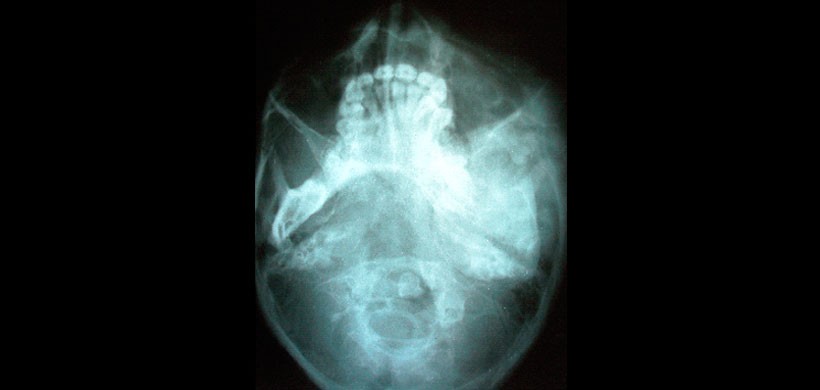

Figura 2: Radiografía submentovertex que revela la expansión de la mandíbula del lado izquierdo.